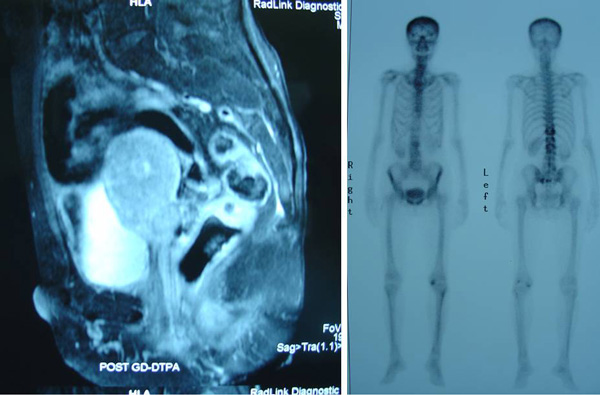

Medical Reports

• 28 March 2012 – EBV Quantitative PCR = Undetectable.

• 30 January 2012 – EBV Quantitative PCR = Undetectable. Less than 715 copies/ ml.

• 19 October 2011 – EBV Quantitative PCR = Detected. 7,997 copies /ml (3.90 log).

• MRI 4 April 2012 – Compared to previous MRI done on 27 February 2011 (note:  The date on this report is obviously wrong. It should have been 21 October 2011??).

1. Interval resolution of nasopharyngeal mass. No evidence of residual disease seen.

2. Interval decrease in retropharyngeal lymphadenopathy, now within normal by size.

3. Interval decrease in cervical lymphadenopathy, most are within normal size criteria except for a right upper level 2 which is borderline in size.